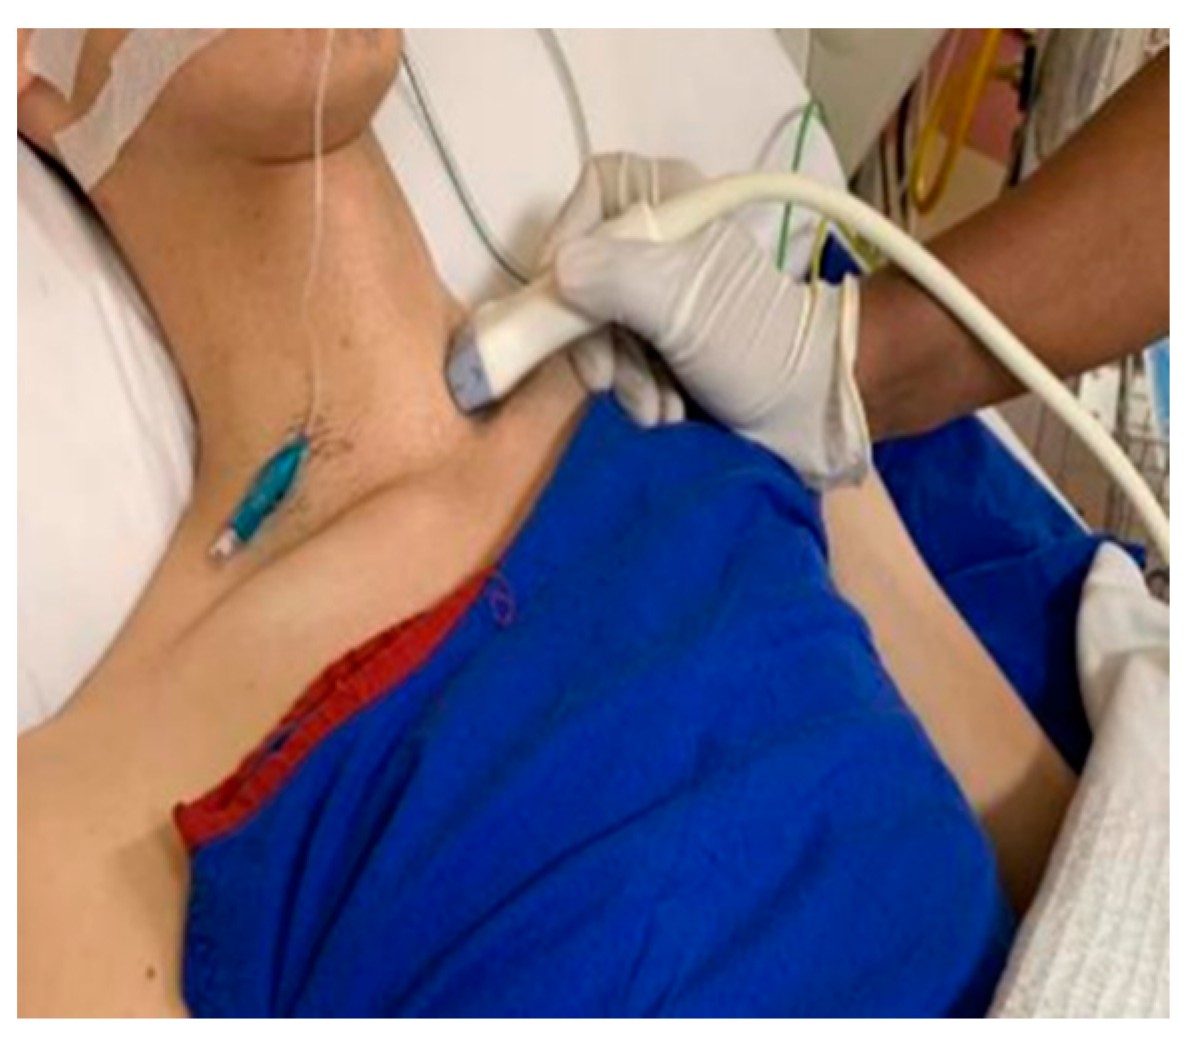

2. Materials and Methods